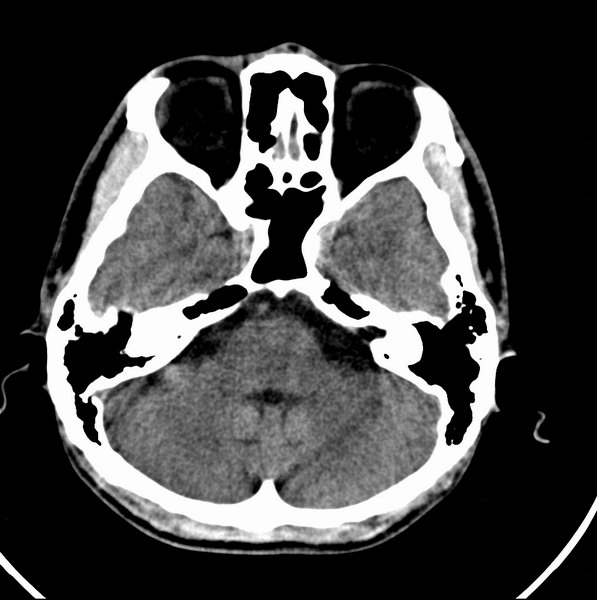

标题: CT21509:额叶低密度影

男、29

突发痴呆,失语,记忆减退,反应迟钝二十小时。

右侧额叶低密度影,边界清晰,无占位效应,符合:额叶皮质脑软化灶。

双额叶脑沟增深增宽,皮质性脑萎缩可以考虑么?

左额叶也有类圆形低密度影,同右侧低密度灶近颅底一层同层,病灶周脑实质密度似稍高,成环状,这个没有问题么?

考虑右侧额叶脑软化灶;建议必要时行mri检查排除其他。

考虑皮质软化灶。不考虑胶质瘤,是因为胶质瘤一般发生于白质内。